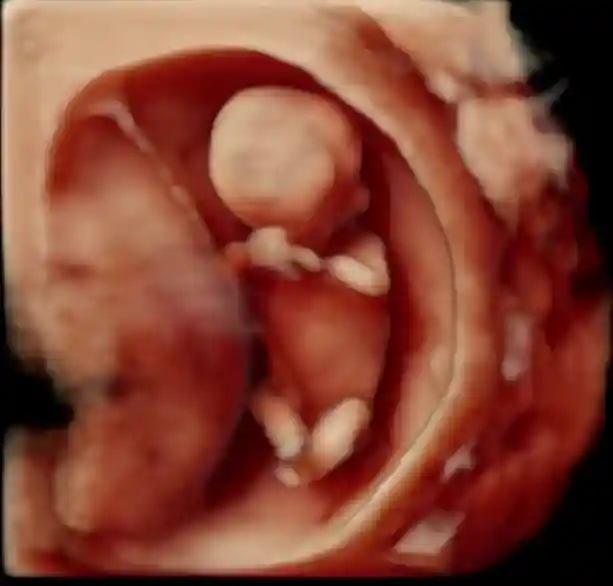

高龄二胎NT秒过~👀 供卵婴儿多少钱

#产检 #孕期

#肚子里的宝宝 #NT #二胎 #接好孕 #胎宝宝在肚子里的状态 #怀孕#胎梦 #胎梦玄学